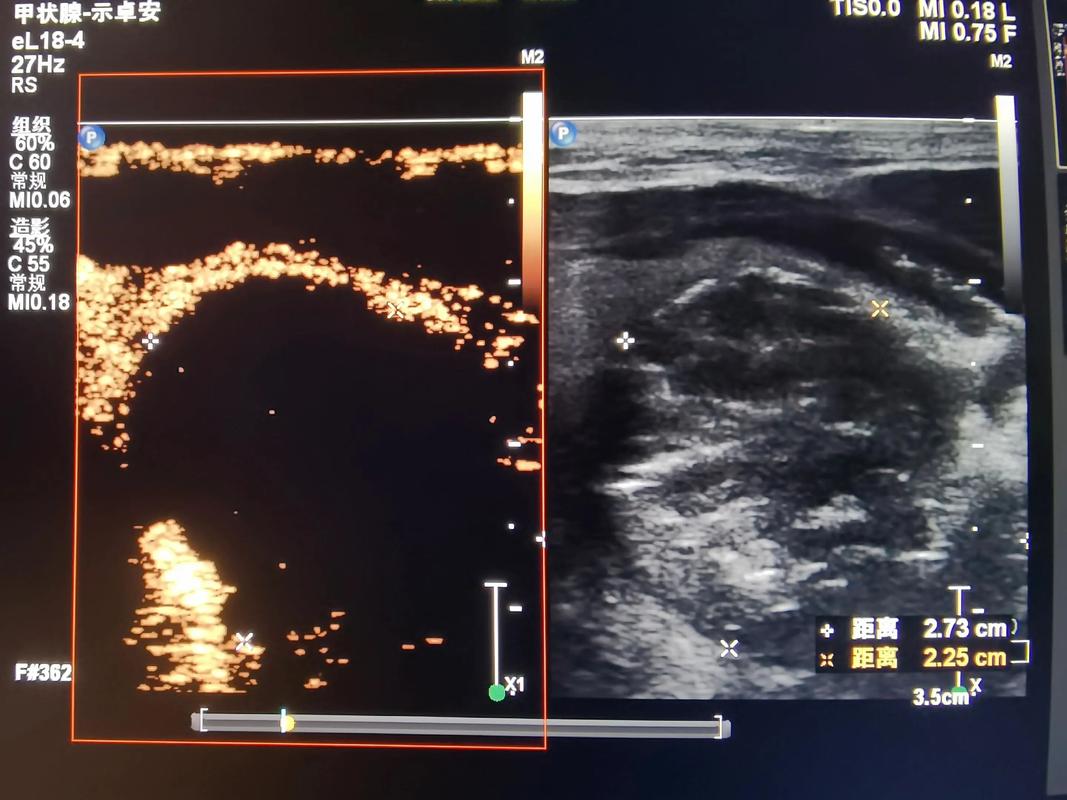

甲状腺结节是指甲状腺组织内出现的一个或多个异常生长的肿块,根据结节的大小、形态、质地和功能等因素,可分为良性结节和恶性结节,良性结节多见于中年女性,恶性结节则相对较少,甲状腺结节的主要症状包括颈部肿块、吞咽困难、声音嘶哑等。

某患者,女,35岁,患有甲状腺结节,经针灸治疗3个月后,症状明显改善,结节缩小,随访1年,未出现复发。